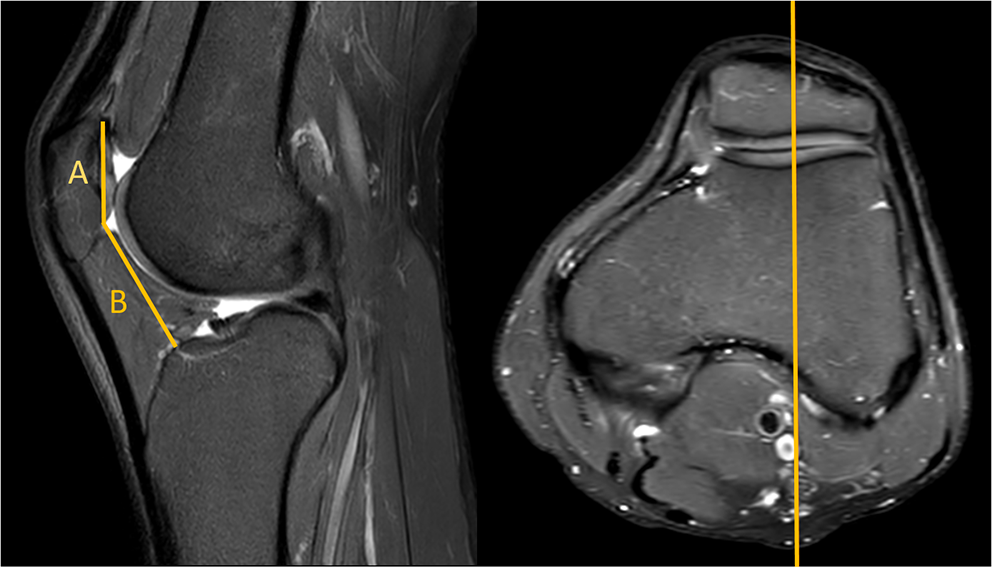

The MRI-based assessment of CD was performed using both the standard single-slice method, and the new two-slice method. The single slice assessment of CD was performed on a single sagital MR-images, utilizing the plane with the maximum length of the articular surface of the patella (Fig. 2). The two-slice method firstly measured the length of the articular surface of the patella at its maximum length (similar to Method 1), and then assessed the distance to the anterior angle of the tibial plateau in the sagittal plane going through the center of the tibial tuberosity (Fig. 3).

Fig. 3

MRI true sagittal view. Caton–Deschamps (CD) index measurement in two slices. A patellar cartilage length (measured in slice with the maximum length of the articular surface of the patella) B distance from Line A to the tibia (measured in slice going through the centre of the tibial tuberosity). CD: B/A